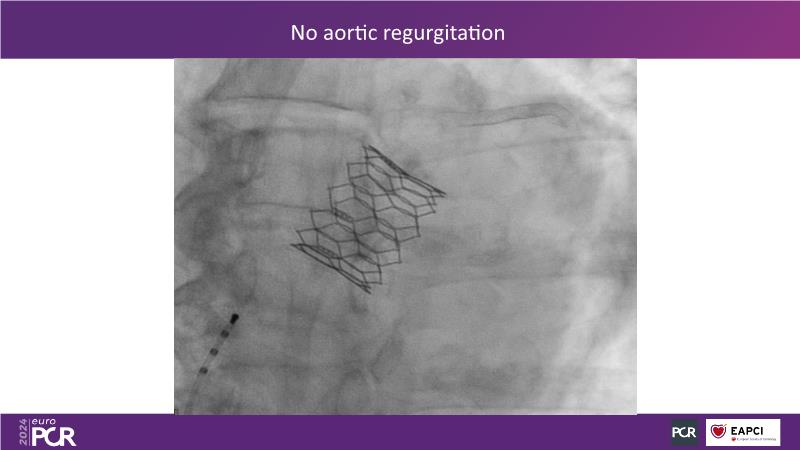

In this session, explore the next-generation balloon-expandable Myval Octacor THV, focusing on its key features, procedural impact, and potential clinical benefits. Understand the procedural steps for planning and implanting it, especially for intermediate and extra-large sizes, using the Octalign technique. Learn about the unmet clinical need of considering TAVI in extra-large annuli, and the clinical significance and relevance of Myval Octacor THV XL sizes. Gain insights from experts on best-in-class TAVI practices, including pre-procedural imaging, sizing rationale, treatment strategies, procedural tips and tricks, and post-procedural management. Additionally, review the latest outcomes from the LANDMARK pivotal RCT and other clinical evidence to date.

- To learn about the novel Myval Octacor THV: a next generation balloon expandable transcatheter heart valve technology - Key features, the procedural impact and potential clinical benefits